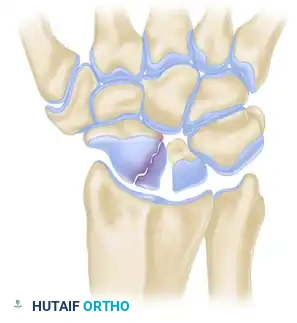

Surgical Anatomy and Fracture Classification

Understanding the three-dimensional orientation of the scaphoid is paramount for successful percutaneous fixation. The scaphoid lies at an oblique angle—approximately 45 degrees to both the sagittal and coronal planes of the wrist.

Fractures are generally classified by their anatomic location: distal pole, waist (middle third), and proximal pole. Waist fractures are the most common, accounting for 70-80% of all scaphoid fractures. Proximal pole fractures have the highest rate of nonunion and osteonecrosis due to the retrograde blood supply.

Clinical Pearl: The central axis of the scaphoid is the biomechanically optimal position for screw placement. A screw placed down the central third of the scaphoid provides maximum stiffness, highest load to failure, and optimal compression across the fracture site.